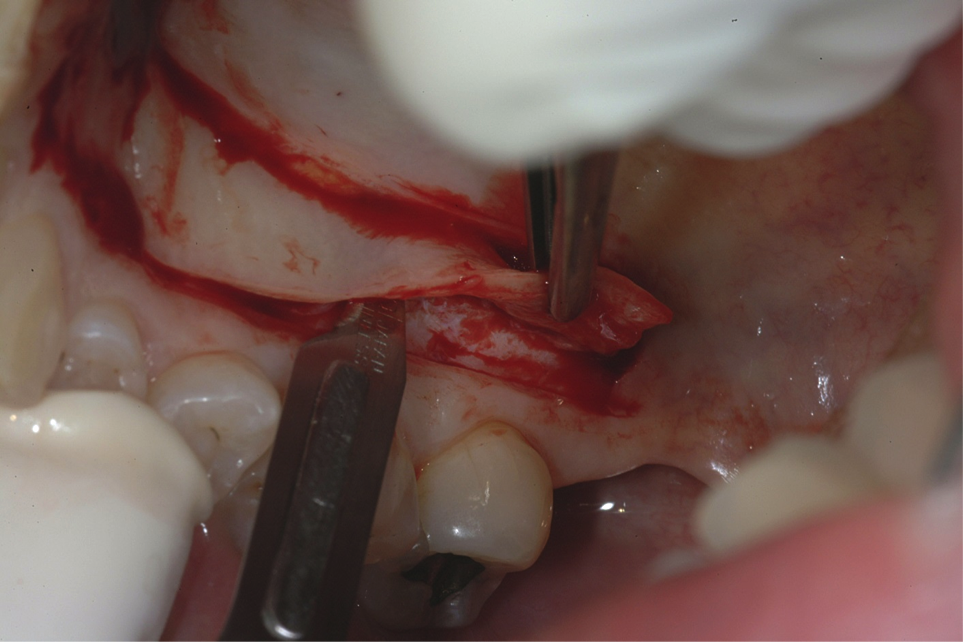

A patient presented with moderate recession requiring root coverage and increased thickness of the alveolar housing (Figure 9). A series of parallel incisions was completed using instruments made specifically for microsurgery; these incisions were performed utilizing high magnification (ie, 5.5 magnification via loupes). The distance between the incisions was roughly the amount of root coverage necessary on the adjacent teeth (Figure 10).25

The isthmus of tissue between the parallel incisions was removed. A split-thickness flap was elevated leaving connective tissue on the bone and providing access for root preparation.

To ensure a smooth root surface, rotary instruments with finishing burs and curettes are used. A glycine air-polishing unit (eg, Air-Flow Master, Hu-Friedy, hu-friedy.com) was used to impart the final smoothing of the roots and remove the smear layer and biofilm.